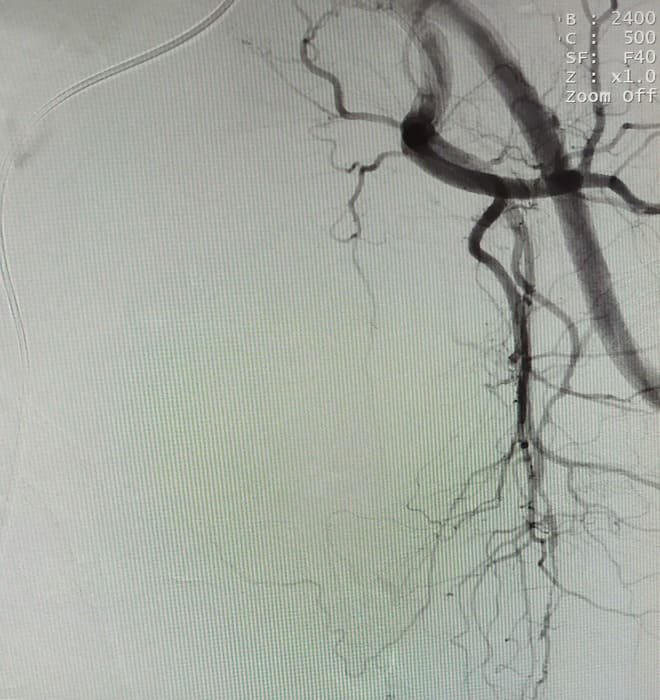

Зазвичай люди літнього віку мають вражені атеросклерозом та звивисті, внаслідок гіпертонічної хвороби судини. Цей випадок не був виключенням, тому нам довелося докласти максимум зусиль, використати високотехнологічне обладнання та інструменти, щоб віднайти цільові судини. На диво, незважаючи на попередню операцію, судинний малюнок рецидивної простати збігався з тим який буває у не оперованих пацієнтів. Тому нам вдалося їх чітко визначити з обох сторін та заповнити емболами. Це доволі кропітка праця, адже щоб викликати ішемію, необхідно поступово виключити кровоплин в усій тканині залози. Полегшувало операцію лише відсутність перетоків артерій на сусідні органи. Це дозволило нам безпечно емболізувати, не боячись негативних наслідків та ускладненнь.

Операція була виконана 28.05.2021. під місцевою анестезією, доступом через прокол в правій стегновій артерії. Вже на протязі тижня зменшилась кількість походів в туалет по маленькому (вночі до 1 разу), полегшилось сечовиділення та покращилось самопочуття хворого.